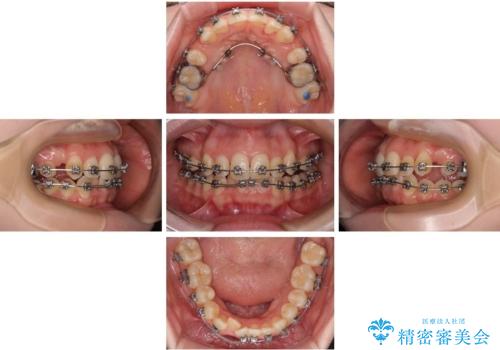

八重歯が気になる。補助装置を併用したワイヤー矯正

- 矯正装置

- メタルブラケット

- 治療計画

- 八重歯が気になるとのことで来院された患者様です。

上顎前歯部はデコボコが強く、歯を並べるためのスペースが不足しているため、左右の第一小臼歯を抜歯することとしました。

また、抜歯して確保したスペースが不足してしまうのを防ぐため、補助装置を併用しています。

矯正治療の前に上下左右の親知らずの抜歯も行いました。